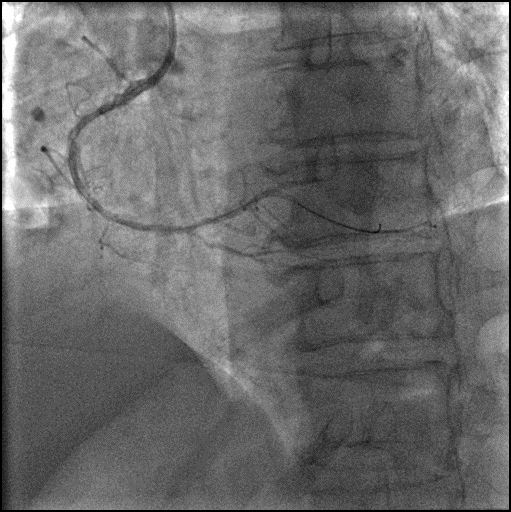

2.5x12mm NC, 3.0x15mm NC球囊反复高压扩张。

6F Telescope™ 导引延长导管加强支撑。

2.5x30mm Integrity Stent, 2.75x38mm Stent。

2.75x12mm NC, 3.0x15mm NC后扩张。